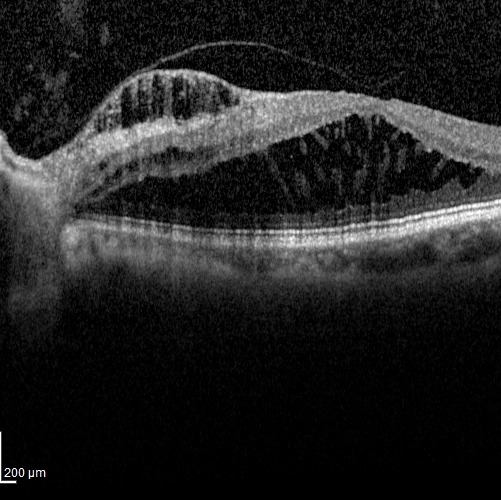

1. Fahim, NM, Sharma M Anatomical Explanation of Optic Disc Pit Maculopathy Associated with Good Visual Acuity Poster Presentation at Annual Optometry’s Meeting 2017 at Washington, DC.

6. Sharma M, Davey PG, Maeda R. Case series describing Retinal Manifestations along with OCT findings amongst patients of Fabry Disease. Poster Presentation at The American Optometric Association Annual Meeting 2015 at Seattle, WA.